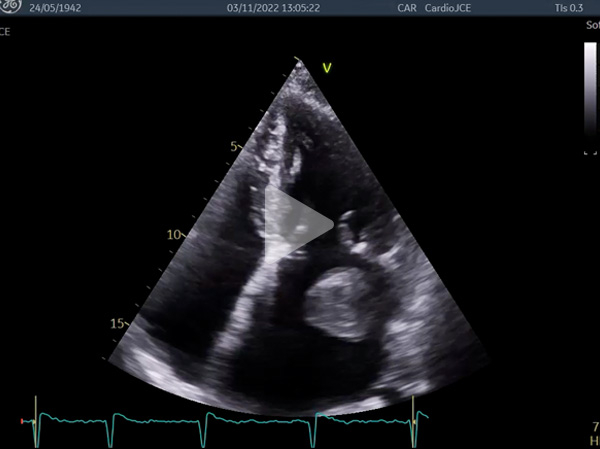

Vidéos 5 à 7 et figure 9 : Masse arrondie de 43 mm de diamètre flottant librement dans l’oreillette gauche avec enclavement périodique dans l’orifice mitral : « ball thrombus »

Vidéo 5

Vidéo 6

Vidéo 7

Figure 8